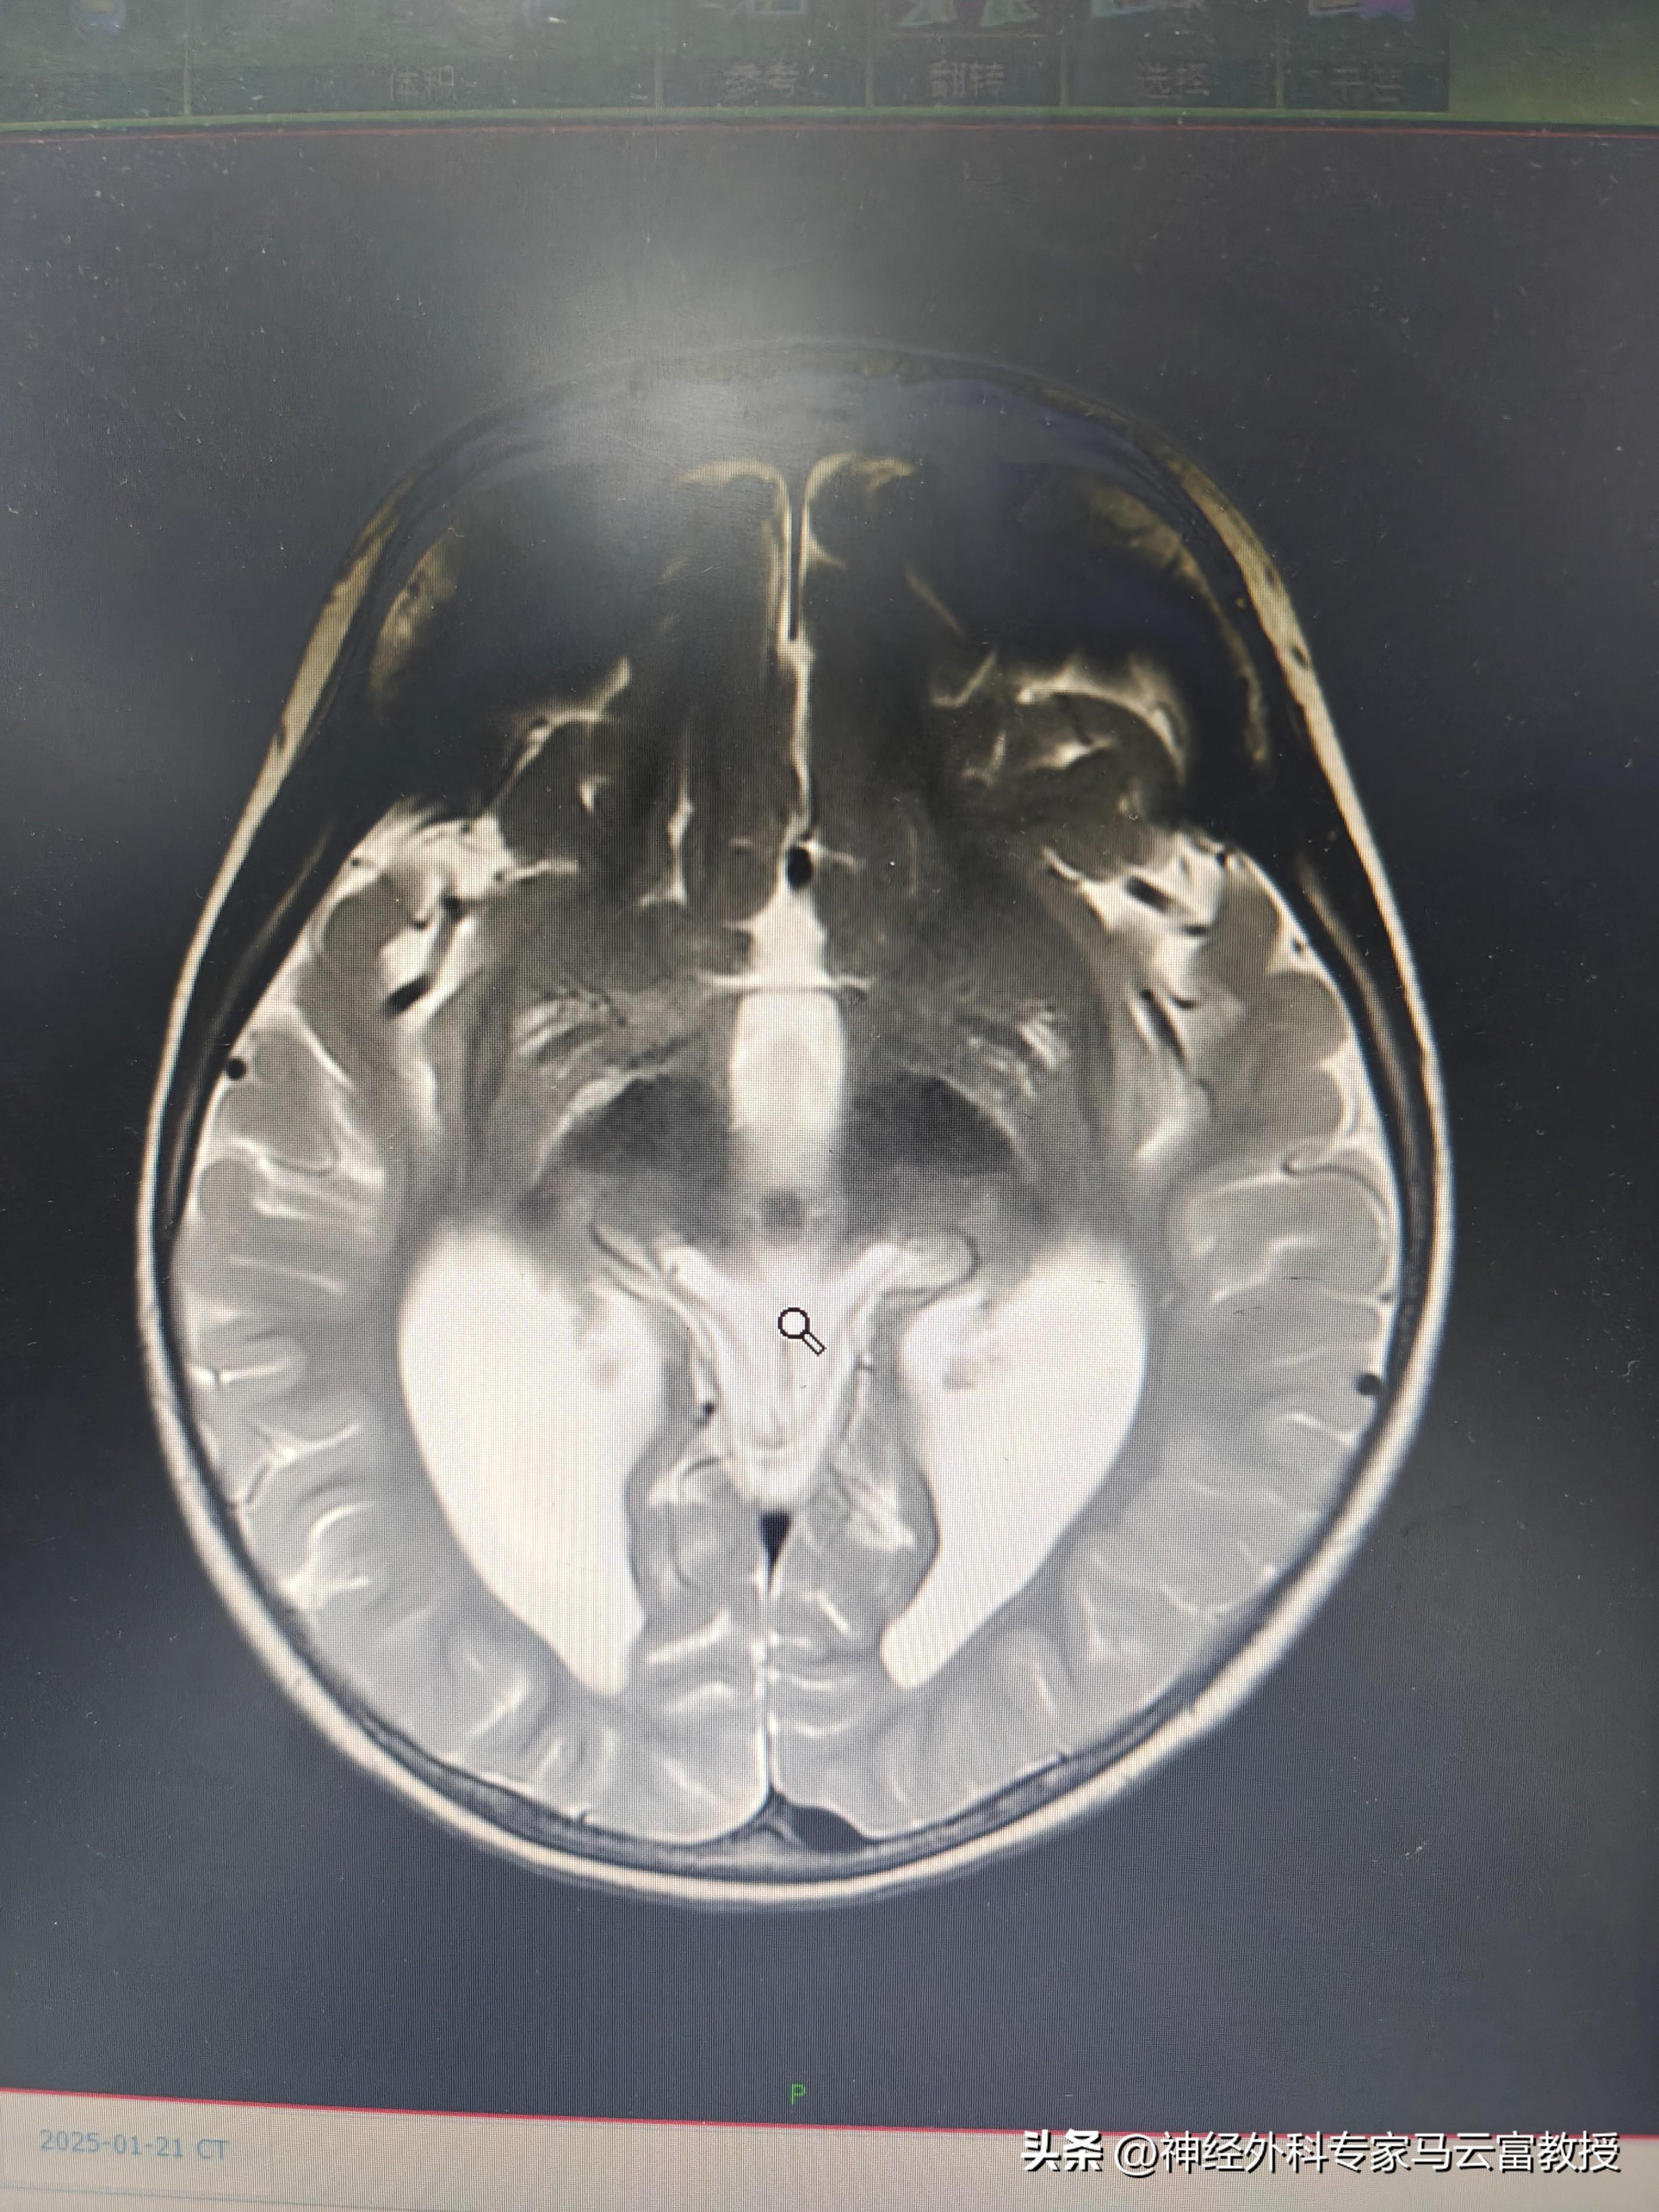

孩子頭圍已達57cm(遠超同齡正常水平),發育也明顯滯後,目前僅能發出 “爸爸”“媽媽” 的簡單音節。在當地醫院檢查時,醫生髮現寶寶側腦室正在逐漸增寬,建議立即轉診至我院進一步診治。

我院神經外科馬雲富主任接診後,通過細緻查體與顱腦 CT 檢查,明確診斷爲幕上腦積水。入院後,團隊完善了腦 MRI + 腦脊液電影成像等精準檢查,最終判斷爲不全梗阻性腦積水,且腰穿提示腦室內壓力不高。綜合評估後,馬雲富主任爲患兒制定了腦室 - 腹腔分流術的治療方案,爲寶寶的大腦 “減壓”,重啓正常發育的可能。